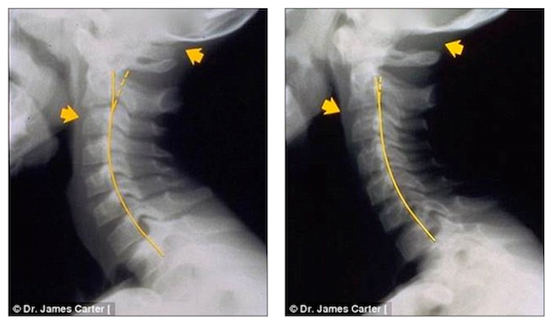

The following X-ray images taken by Dr. Carter give a look at how badly text neck is affecting children.

He even had one seven-year-old patient with “text neck” symptoms, pictured before (left) and after (right) treatment.